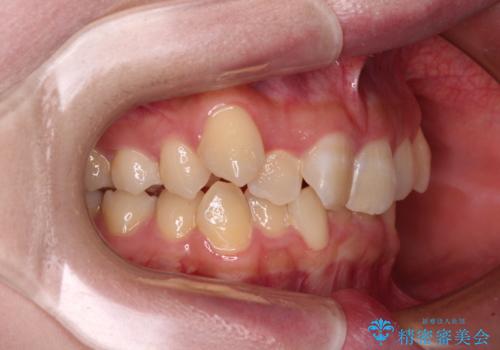

- 上下の八重歯を気にして来院された患者様です。

非抜歯矯正で歯列を整えると、治療後に口元が今よりも突出する可能性が高かったため、上下左右の小臼歯4本を抜歯し、ワイヤー装置にて矯正治療を行うこととしました。

右上の八重歯の影響で、右側は上顎歯列が前方位の咬み合わせとなってしまっていたため、上顎は第一小臼歯を、下顎は第二小臼歯を抜歯することで咬み合わせや上下正中を調整することとしました。

第二小臼歯抜歯の治療となったため、やや時間はかかりましたが、概ね予想通りの期間で治療を終えることができました。